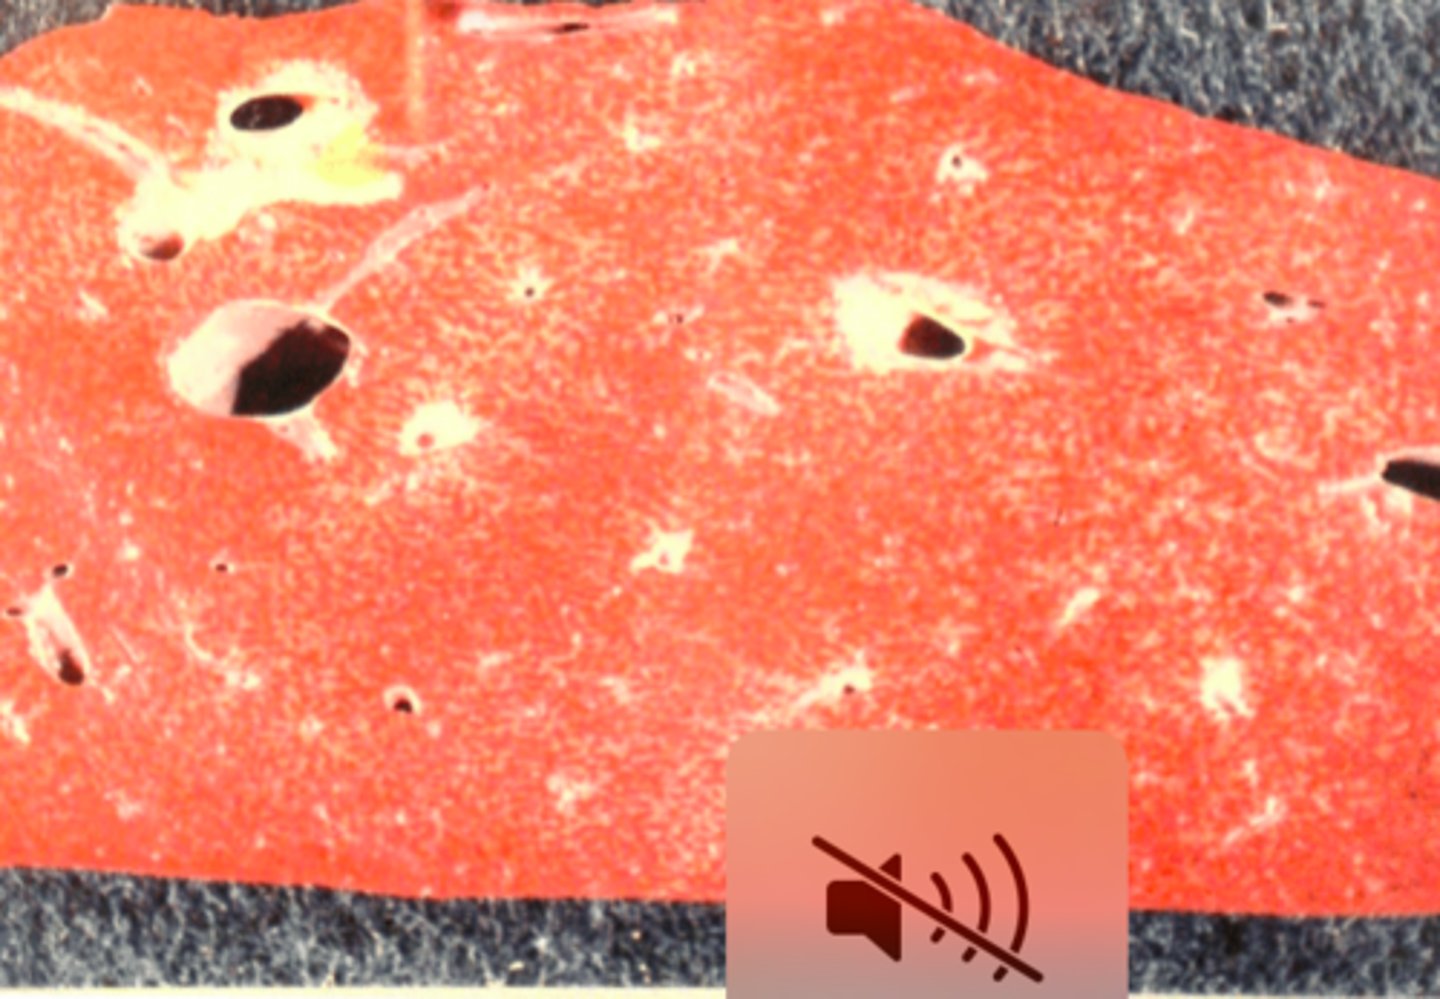

Kronisk multifokal, fibrøs, interstitiel hepatitis

Ætiologi: migration af Ascaris suum larver

Lever fra svin, hvad er den patoanatomiske diagnose og ætiologien?

Kronisk multifokal, fibrøs, interstitiel hepatitis

Ætiologi: migration af Ascaris suum larver

Lever fra svin, hvad er den patoanatomiske diagnose og ætiologien?